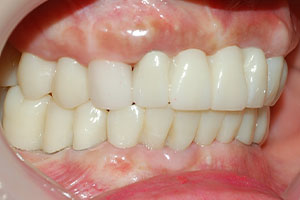

치료증례 전후사진

Before & After